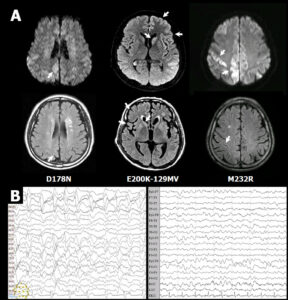

CJD profiles of MRI and EEG from probable CJD patient.

Micrograph showing spongiform degeneration (holes/vacuoles) in the cerebral cortex of a patient who had died of Creutzfeldt-Jakob disease; the scale bar = 30 microns (0.03 mm).

FLAIR-MRI of Creutzfeldt–Jakob disease.

- CJD_profiles_of_MRI_and_EEG_from_probable_CJD_patient © Bo-Yeong Choi1 , Su Yeon Kim1 , So-Young Seo1 , Seong Soo A An2 , SangYun Kim3 , Sang-Eun Park4 , Seung-Han Lee5 , Yun-Ju Choi5 , Sang-Jin Kim6 , Chi-Kyeong Kim1 , Jun-Sun Park1 and Young-Ran Ju is licensed under a CC BY (Attribution) license